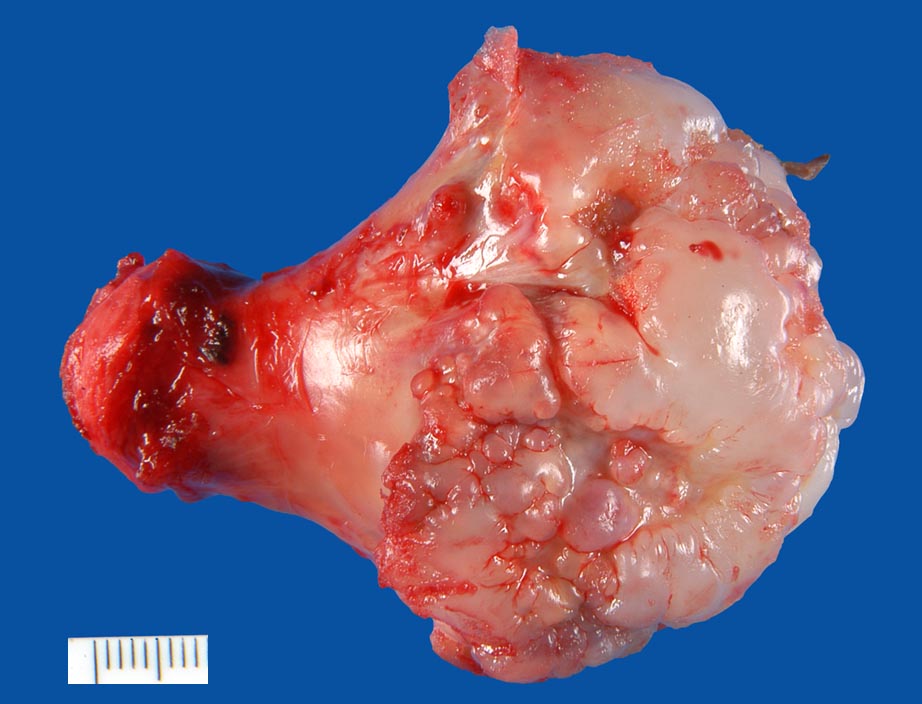

PathoPic ID 9478 - Osteochondrom

Osteochondrom

benigner Tumor

Knochen, Femur

Knochen, Knorpel, Gelenke

Der mediale Femurkondylus ist blumenkohlartig aufgetrieben und zeigt eine glasige gräuliche Oberfläche.

Auf lamellierenden Schnitten ein kortikaler Knorpelüberzug von max. 6,5mm Breite.

Gestieltes Osteochondrom distaler Femur rechts medial.

Makroskopie

13

männlich